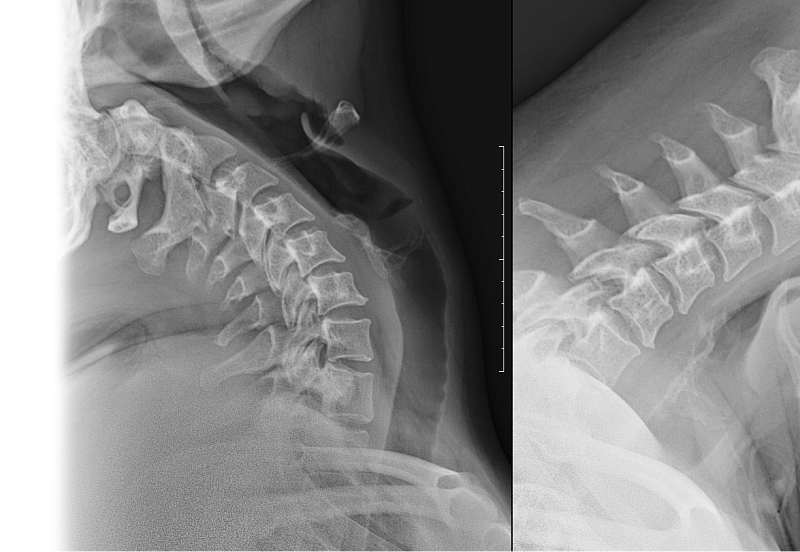

Рентгенография одного отдела позвоночника: функциональные пробы Рентгенография одного отдела позвоночника: функциональные пробы

Рентгенография одного отдела позвоночника: функциональные пробы – важный метод скринингового исследования, который позволяет оценить состояние отдела позвоночника.

Диагностическая услуга выполняется в двух проекциях.

18.7 Рентгенография (цифровая) одного отдела позвоночника: функциональные пробы (сгибание, разгибание, запись на диск) 3 600 ₽